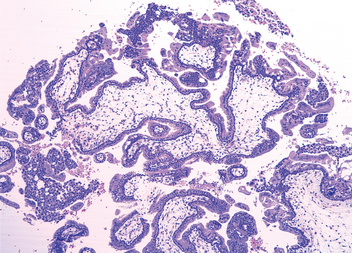

A clinical condition referred to as pseudomyxoma peritonei is defined by extensive mucinous ascites, cystic epithelial implants on the peritoneal surfaces, adhesions, and frequently mucinous tumor involving the ovaries (Fig. 22-40). Pseudomyxoma peritonei, if extensive, may result in intestinal obstruction and death. Historically, it was thought that many cases of pseudomyxoma peritonei in women were due to primary ovarian mucinous neoplasms. However, recent evidence points to the presence, in most cases, of extraovarian (usually appendiceal) primary mucinous tumor with secondary ovarian and peritoneal spread (Chapter 17).88 Because the majority of primary mucinous ovarian tumors are unilateral, bilateral presentation of mucinous tumors always requires exclusion of a non-ovarian origin.

image

FIGURE 22-40 A, Pseudomyxoma peritonei viewed at laparotomy revealing massive overgrowth of a gelatinous metastatic tumor originating from the appendix. B, Histology of peritoneal implants from an appendiceal tumor, showing mucin-producing epithelium and free mucin (arrow).

(A, Courtesy of Dr. Paul H. Sugarbaker, Washington Hospital Cancer Center, Washington, DC.)